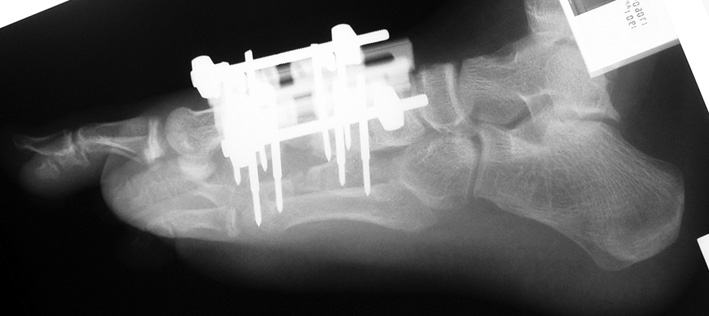

Doğuştan metakarp ve metatars kısalıklarının redavisi için pek çok teknik tanımlanmakla birlikte en çok akut uzatma sonrası kemik uçlarına greft konması ve distraksiyon osteogenezi (kallotasis) kullanılmaktadır. 1 cm.den daha fazla uzatma gereken olgularda kallotasis yöntemi önerilmektedir. Kliniğimizde de metatars ve metakarp uzatma için unilateral eksternal fiksatör ve sirküler eksternal fiksatör yardımıyla distraksiyon osteogenezi yöntemi tercih edilmektedir.